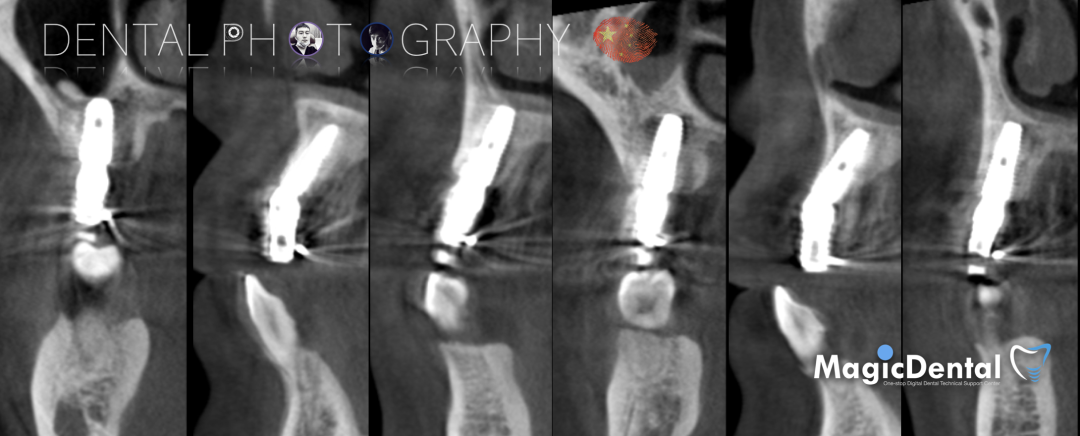

术前CBCT

CBCT显示全口牙槽骨水平吸收严重,下颌骨量保存大于上颌

术后三个月复查CBCT